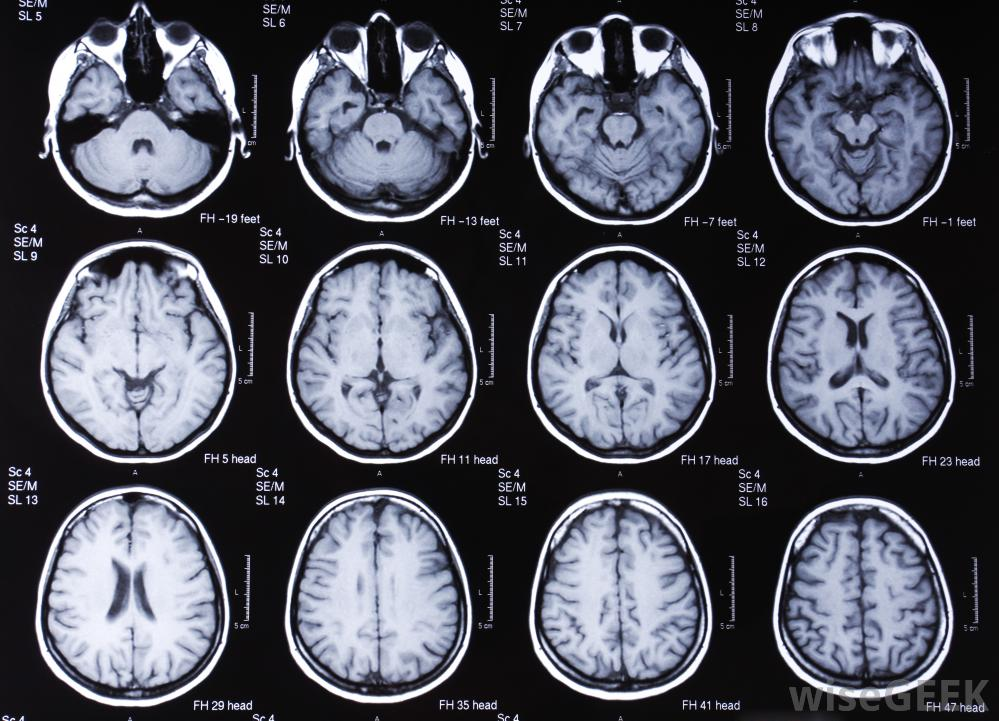

Процесс постановки диагноза по результатам МРТ включает несколько этапов. Сначала врач-рентгенолог или специалист по лучевой диагностике проводит расшифровку полученных снимков. Эти снимки демонстрируют изменения в тканях, наличие аномалий, воспалительных процессов, новообразований и других патологий. На основании анализа изображений и медицинской истории пациента специалист формирует окончательное заключение.

При исследовании головного мозга с помощью МРТ можно обнаружить такие патологии, как инсульты, рассеянный склероз, опухоли, травматические повреждения и инфекции. В области позвоночника метод позволяет выявить протрузии и грыжи межпозвоночных дисков, сдавления нервных корешков и дегенеративные изменения позвонков.

При анализе результатов учитывается локализация обнаруженных нарушений, их размер, структура, наличие изменений в окружающих тканях и динамика процесса, если исследование проводится повторно. Важно, что некоторые патологические изменения могут быть вариантом нормы или возрастными изменениями, не требующими лечебных мероприятий.